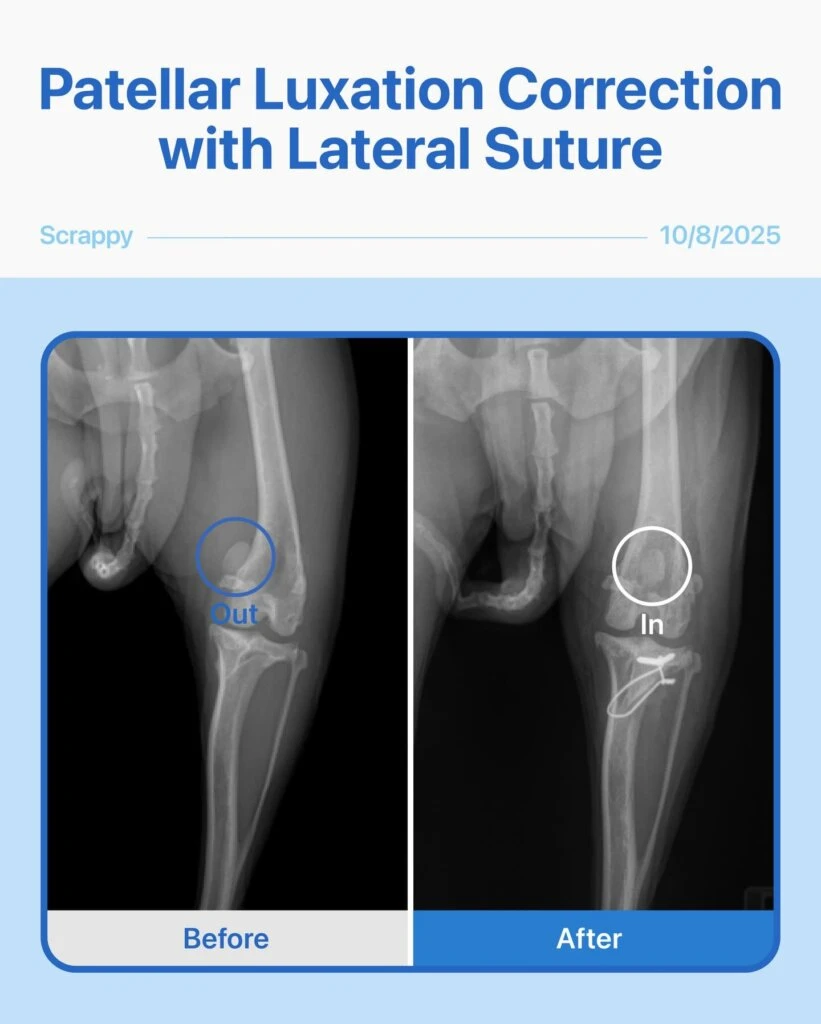

This brave 11-year-old Chihuahua mix came in after his owner noticed his knee kept dislocating. Radiographs showed a severe Grade 4 patellar luxation and a torn cruciate ligament.

Given his age, size, and breed, combining patellar luxation correction with lateral suture surgery was the safest and most effective option for him.